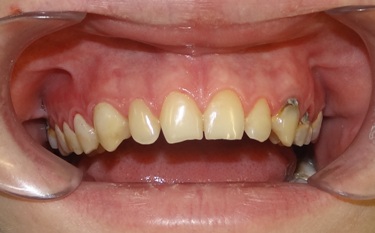

Pacjent z dużymi potrzebami leczenia stomatologicznego. Po stronie prawej widoczne są stare wypełnienia, nad którymi jest zapalenie dziąsła. Po stronie lewej zęby przed leczeniem, również z zapaleniem dziąsła brzeżnego. W naszym gabinecie wymieniono wypełnienia na czterech górnych siekaczach. Uzyskano znaczącą poprawę estetyki siekaczy górnych i stanu dziąseł nad tymi zębami. Pacjent kontynuuje leczenie.